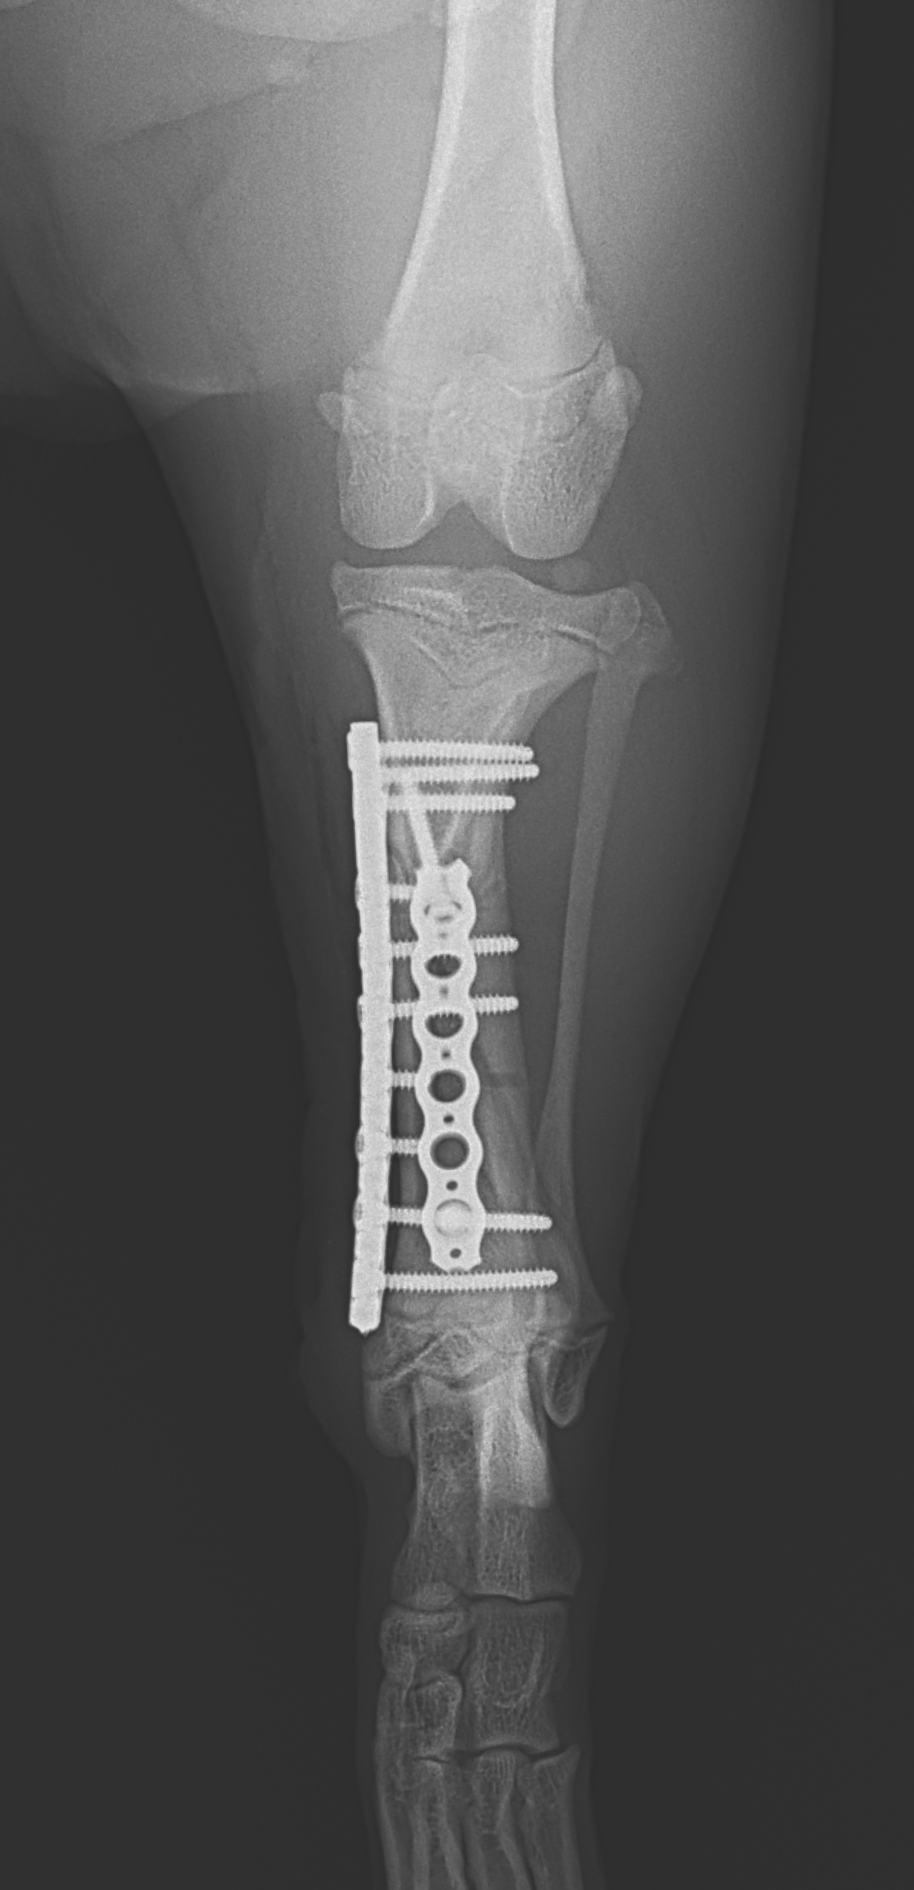

若齢犬の脛骨らせん状骨折

パピーがアクシデントで脛骨を骨折したとのこと。かかりつけ医から固定術の依頼がありました。長くらせん状に骨折ラインが確認されました。Titanium Locking Plateを使いオルソゴナル・ダブルプレート法で固定術を行いました。また、このワンコの脛骨の形状は特殊であり、近位の骨幅は広く確保できるのですが、骨幹部は湾曲が強くプレーティングには工夫が必要です。しばらく安静が必要ですがまたドッグランで走れるようになれます。